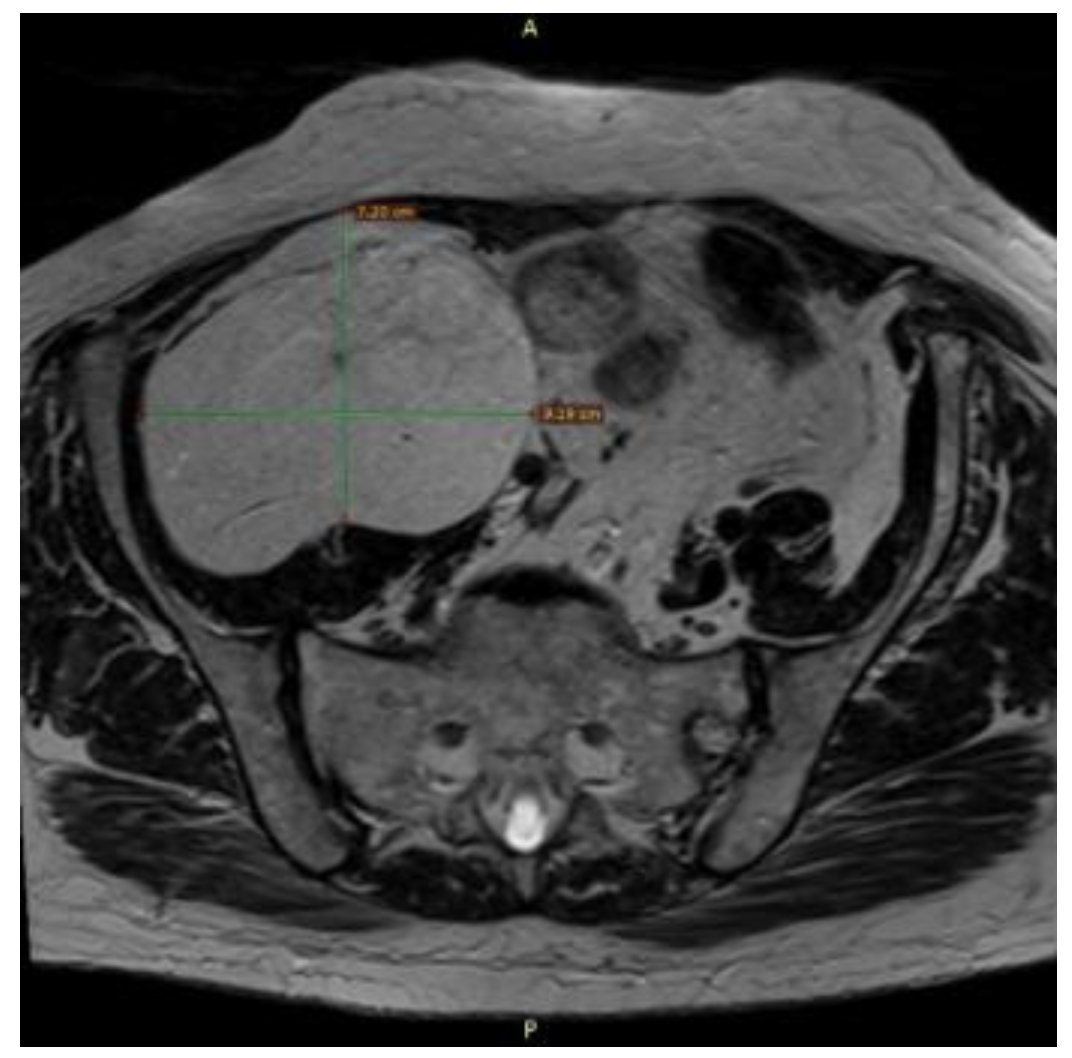

2. Case Presentation